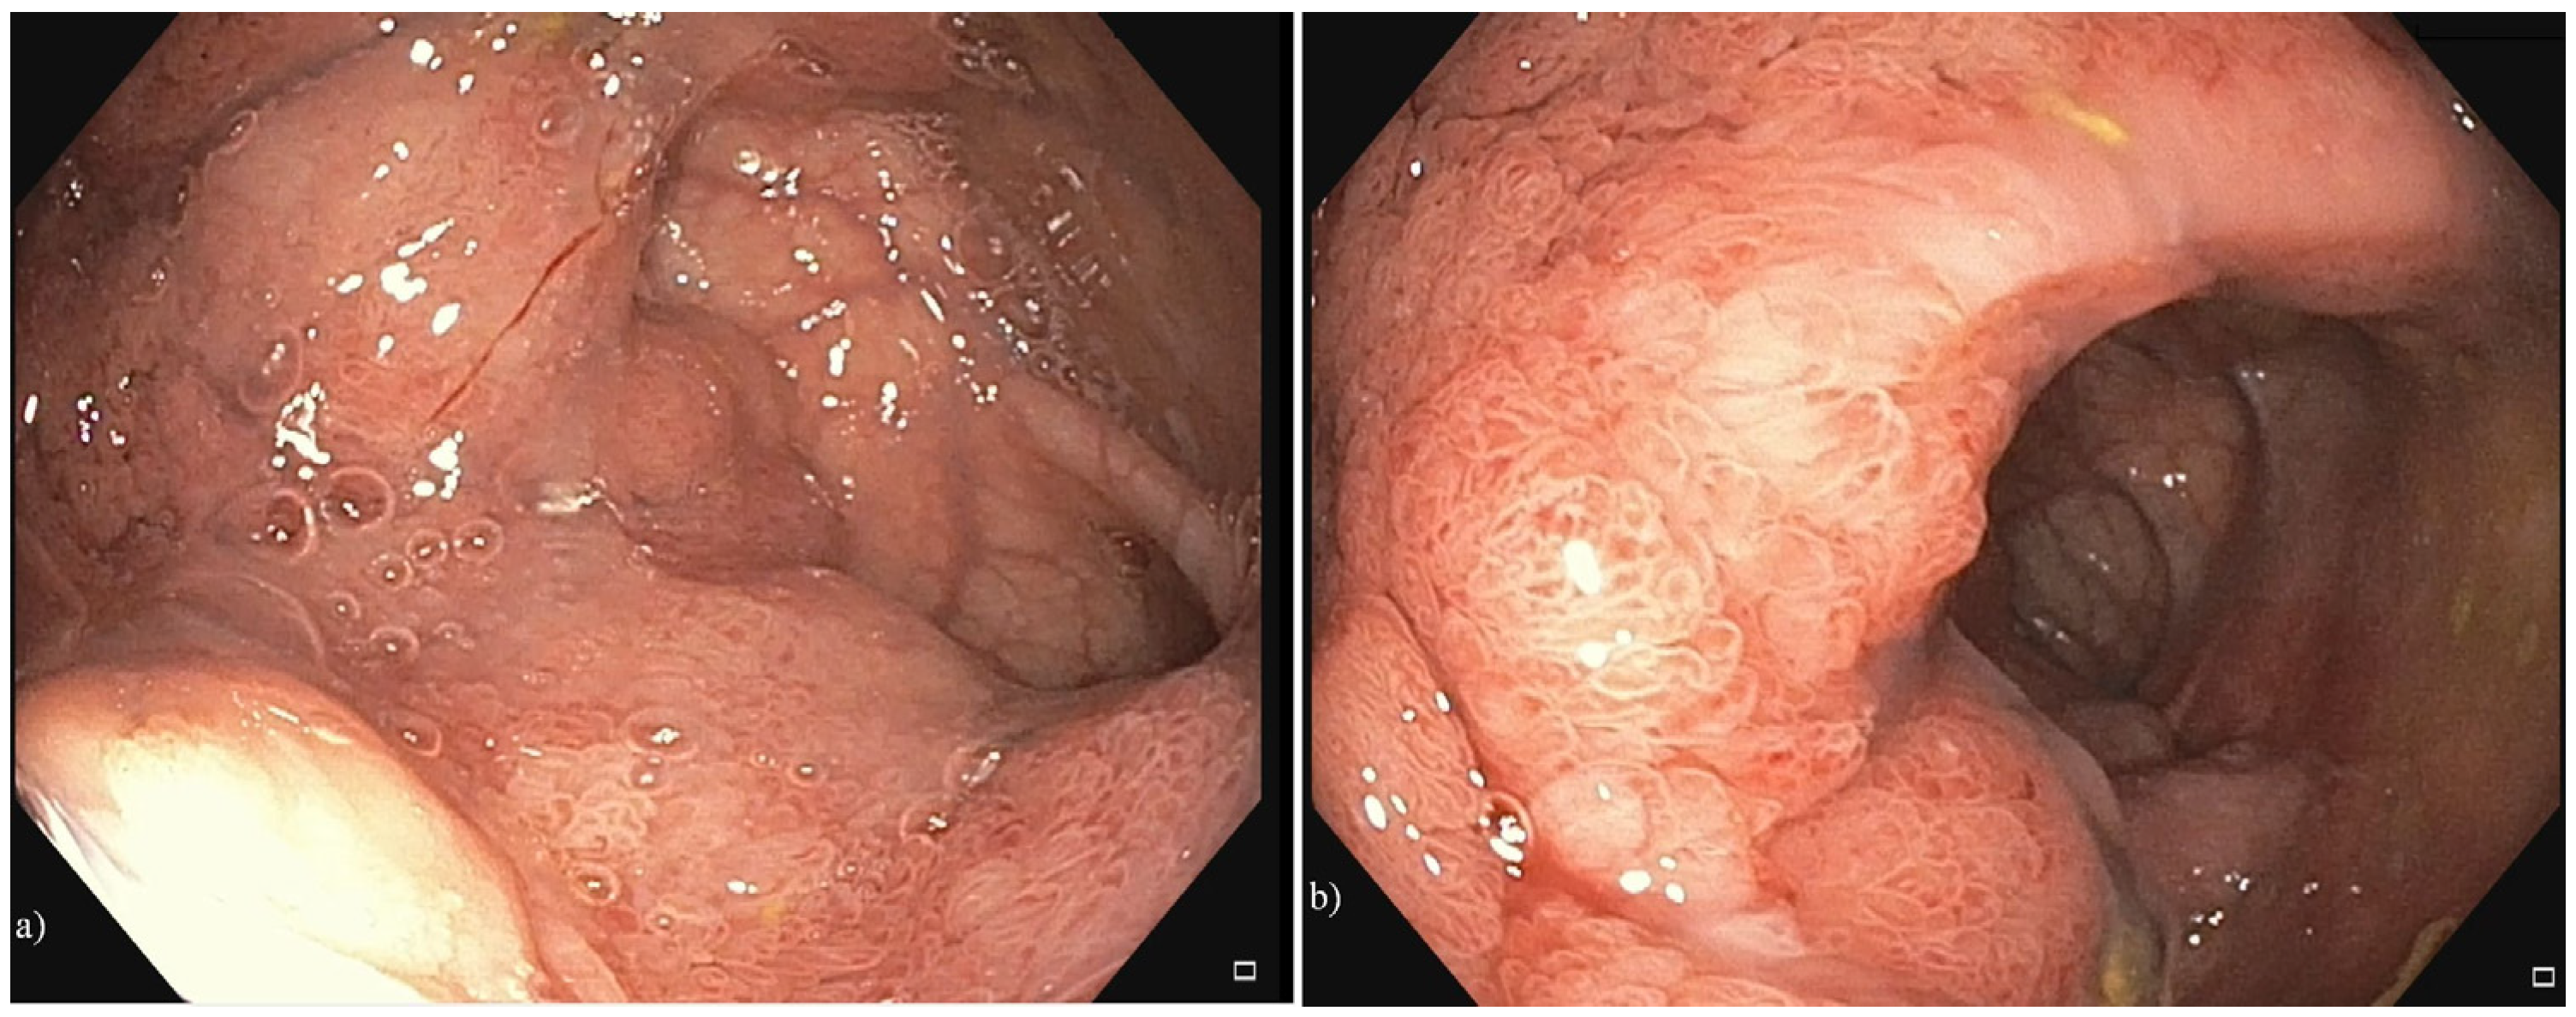

2. Case Presentation